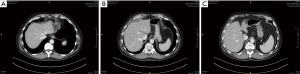

Repeat hepatectomy is considered challenging due to a few reasons. Exposure for a repeat hepatectomy may be difficult due to post-operative adhesions following previous liver resection. Hypertrophy of the residual liver as well as alterations of the hepatic anatomy from previous hepatectomy may post significant challenging in the vascular and biliary ductal planes (Figure 6A,B,C,D). Such challenges may potentially increase the risk of morbidity and mortality in repeat hepatectomy. Yet, most of the studies showed that it is feasible to perform repeat hepatectomy in CRLM with reasonably low morbidity and mortality (124,125). It is a fine balance between parenchymal preserving and anatomical resection of the liver metastatic lesions. The most important consideration should be the ability to achieve R0 resection. Sparing more liver parenchyma is crucial to prepare for possible future need of another liver resection. In event that repeat liver resection is no longer possible due to limitations in liver vascular and biliary anatomy or inadequate FLR, could there be a role for liver transplantation in the future? There is very little evidence to support this strategy at this point in time but the body of evidence is growing at this juncture (see below on liver transplant in CRLM).